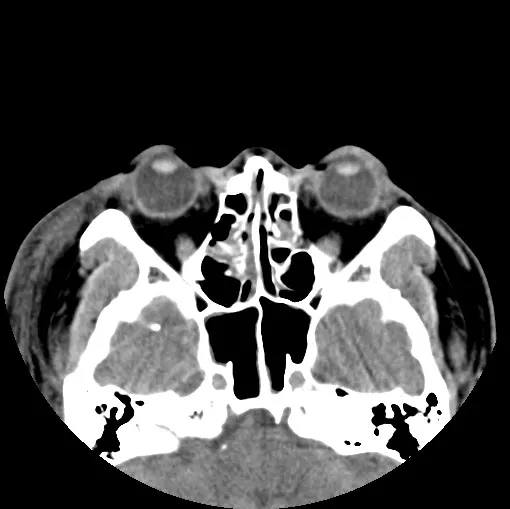

鼻骨骨折(Nasal bone fracture)是面部骨折中最常见的一种,其发生率在所有面部骨折中占据很大的比例。鼻骨骨折一般可以通过X光片或CT扫描确诊。虽然大多数鼻骨骨折都是轻微的,但若处理不当,可能会引发一系列并发症,甚至影响美观和呼吸功能。

鼻骨骨折主要由外力冲击导致,常见成因包括交通事故、运动损伤、意外跌倒及暴力事件。鼻骨骨折的症状包括鼻部疼痛、肿胀、出血、变形以及呼吸困难。对于一些严重的鼻骨骨折,甚至可能伴有脑震荡或其他面部骨折。